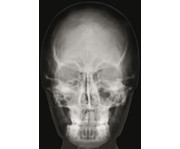

- 18 Detailaufnahmen

Halten Sie diese lebensgroßen Röntgenaufnahmen einer jungen erwachsenen Person gegen das Licht (z. B. die Fensterscheibe). Auch auf einem Lichttisch lassen sich die Aufnahmen gut anschauen. Auf diesen Röntgenaufnahmen können Ihre Schülerinnen und Schüler einen echten Skelettaufbau betrachten. Nach genauer Sichtung der 18 verschiedenen Detailaufnahmen können die Teile zu einem ganzen Skelett zusammengelegt werden.